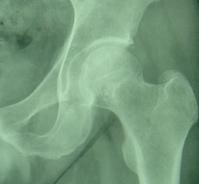

骨壞死而對於骨壞死,人體在任何部位都有可能發生,僅就缺血性壞死已經發現40餘處,而股骨頭壞死發生率最高,這主要由生物力學和解剖學方面的特點來決定的。因股骨頭為終末血管呈扇狀20--25支,在頭頸交界形成動、靜脈環,其來源於鏇股內外動脈。 (1)負重大。髖關節是人體最大的關節,支撐著整個軀幹的重量,頭與臼之間壓力必然增大,長期保持著這種較大的壓力,不但容易造成結構上的損傷,而且影響局部的血液環。 (2)剪力在。髖關節不同於其它負重關節那樣兩骨端關節力線垂直,股骨幹與股骨頭頸之間形成132度的角,軀幹的重力是由髖臼通過股骨頭,頸移行至股骨幹,力線不垂直,就形成了剪力。因此,頭頸所承受的生理壓力要比其它關節大得多。 (3)活動範圍大。髖關節的活動範圍僅次於肩關節,伸展、內收、外展、鏇轉等。能完成各軸向運動,損傷的機會也較多。 (4)血供少。股骨頭的血供主要依靠囊外動脈環發出的外側支持帶和內側支持帶動脈,血管的吻合支量少且薄弱,當一支血管被阻斷而另一支不能及時代償時,即會造成股骨頭的供血障礙。

骨壞死股骨頭壞死,又稱股骨頭缺血性壞死或股骨頭無菌性壞死。它以髖關節疼痛、跛行為主要臨床表現。但早期往往僅表現為膝關節、大腿內側疼痛而被誤診。

造成股骨頭壞死的原因大致有兩類:一類是創傷性,多因髖部受傷後引起股骨頭骨折、股骨頸骨折、髖關節脫位,以及沒有骨折脫位的髖部軟組織損傷。其中,由股骨頸骨折而發展成股骨頭壞死者最為多見,約占股骨頭頸骨折的30%左右,而且患者年齡越小,發生股骨頭壞死的機會越多,這主要是因為創傷引起股骨頭滋養血管中斷或瘀阻,股骨頭缺血而造成;另一類是非創傷性的,包括長期大量使用糖皮質激素(是因為某些疾病的治療需要,也有的時候是誤用激素)、酒精中毒、減壓病等等,這些因素有的可以造成血液粘稠度增加,也可以導致血管壁增厚、管腔狹窄。不論是創傷性和非創傷性的因素,最終的結果一是造成動脈供血不足,二是造成靜脈瘀阻,而後者又可以引起骨內壓升高,進一步加重動脈供血不足,最終導致股骨頭缺血、缺氧、骨細胞變性、壞死。

是診斷該病最簡單、最實用的方法,但敏感性差,早期單憑X線片不易診斷。骨壞死早期表現為骨質正常或輕度疏鬆,也可出現病變區骨密度相對均勻增高現象,隨後可見負重區有楔狀硬化帶或骨組織囊性病灶形成,進一步出現與關節面平行的“新月狀透亮帶”,關節間隙增寬。最後出現軟骨下骨板及關節面塌陷,骨輪廓改變,階梯狀不連續,骨壓縮加重,同時髖臼關節面也受損,關節間隙狹窄、骨贅形成,整個關節呈現退行性關節炎改變。